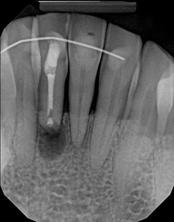

Non-surgical root canal treatment:

Before

Immediately After

6-month follow-upThis patient presented with pain when chewing. Diagnostic testing was done and determined it was the lower molar. The diagnosis was: pulpal necrosis, symptomatic periradicular periodontitis. Root canal treatment was performed with laser disinfection. The tooth had a crown and we accessed the tooth through the crown. We saved the tooth and the crown.